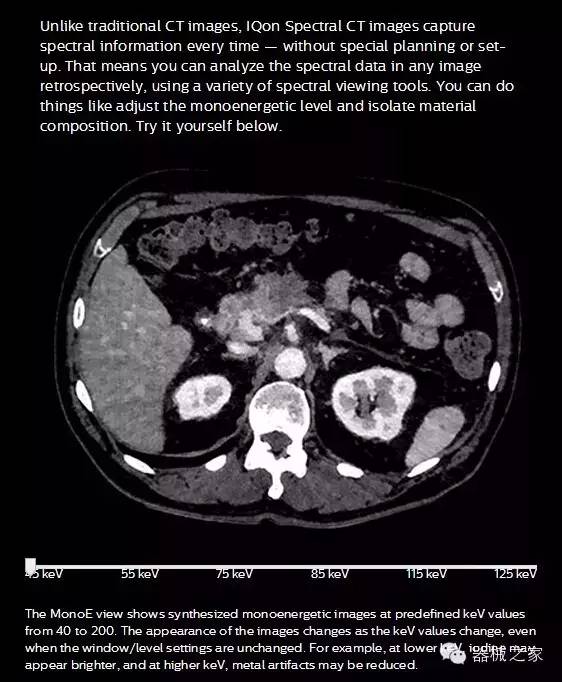

IQon光譜CT能夠按照需求提供光譜量化和工具,并能通過簡單工作流程、在低劑量下對(duì)結(jié)構(gòu)進(jìn)行定性分析

IQon光譜CT -- 是業(yè)界首臺(tái)以探測器為成像基礎(chǔ)的光譜CT,它可以在單次常規(guī)掃描下獲得傳統(tǒng)解剖影像及光譜功能影像。不僅可以提供精準(zhǔn)的診斷信息,還可簡化工作流程、在低劑量下完成定量與定性分析。